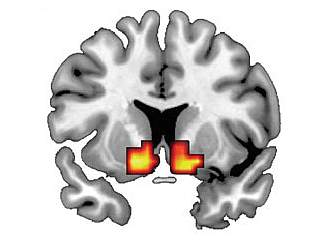

In the second experiment, participants played a computer a game in which they could win money. Their brains were scanned using functional MRI as they anticipated their monetary rewards. The findings were reported on March 14, 2010, in the advance online edition of Nature Neuroscience.

The results in both cases show that people with higher scores for impulsive and antisocial traits had greater responses in the dopamine reward areas of the brain. In the first study, the amount of dopamine released was up to 4 times higher in those who scored high for these traits, compared to those with lower scores. In contrast, scores for the emotional and interpersonal aspects of psychopathy did not correlate with the brain's reward responses.